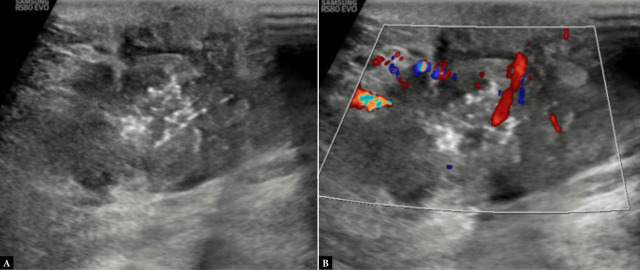

Results: A significant association between posterior acoustic features and molecular subtypes was seen. Posterior acoustic shadowing was associated with progesterone receptor status with an odds ratio (OR) of 36.58, confidence interval (CI) of 5.527-866.1, and p <0.001. The luminal type A molecular subtype was significantly higher in the posterior acoustic shadowing group (10 cases; 52.63%) with an OR of 3.85, CI of 1.12-13.98, and p of 0.02. The proportion of patients with triple-negative molecular subtype (9 cases, 50%) was significantly higher in the posterior acoustic enhancement group, with an OR of 29.42, CI of 4.117-725.4, and p <0.001. Tumors with circumscribed margins were also highly suggestive of the triple-negative molecular subtype [OR of 5.12, CI of 1.16-24.85, and p of 0.03]. The association between the presence or absence of vascularity and its type with molecular subtypes failed to show statistical significance in our study, although vascularity was more frequently observed in triple-negative molecular subtype and luminal type B Her+ve cases.

Conclusion: Certain sonographic features are associated with the estrogen/progesterone receptor hormone receptor status and molecular subtypes of breast cancer. With validation of this association, ultrasound may serve as a basic imaging modality for predicting molecular subtypes of breast cancer even in remote areas, where immunohistochemistry hormone receptor and HER2 testing are not available.